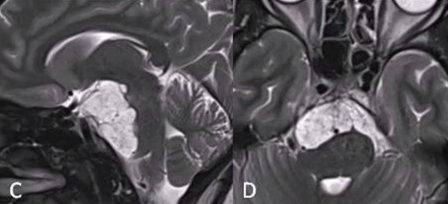

采用联合内窥镜鼻内入路(EEA)切除硬膜外部分重量,对于硬膜内部分肿瘤采用经颅入路,以降低脑脊液漏和神经血管损伤的风险。首先,进行内镜鼻内活检,显示典型的脊索瘤。然后,她接受了内镜经鼻入路手术,从硬膜外部分切除到斜坡和海绵窦部分的肿瘤(图C、D)。